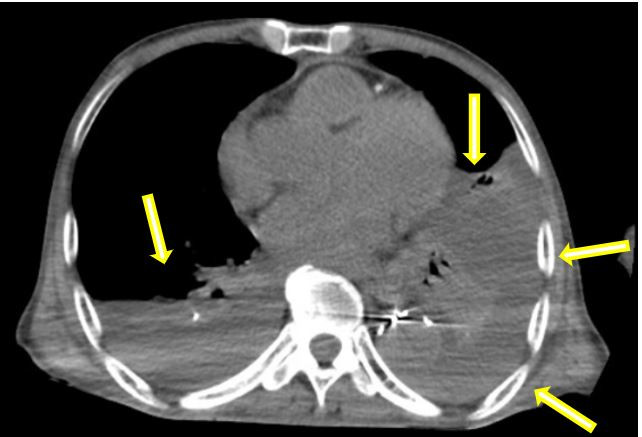

原胸主動(dòng)脈支架近端出現(xiàn)明顯內(nèi)漏(箭頭示)

巨大假性動(dòng)脈瘤壓迫左肺(箭頭示)

在患者轉(zhuǎn)運(yùn)過程中,血管外科急診團(tuán)隊(duì)、影像科、麻醉科、胸心外科、導(dǎo)管室、輸血科等相關(guān)科室已著手做好了急診相關(guān)預(yù)案。從患者的急診CTA上可以看到原有的胸主動(dòng)脈支架因血流動(dòng)力學(xué)影響,出現(xiàn)了近端Ⅰ型內(nèi)漏,大量血液經(jīng)由支架與主動(dòng)脈間的縫隙進(jìn)入假性動(dòng)脈瘤腔內(nèi),左側(cè)胸腔出現(xiàn)大量血腫,甚至出現(xiàn)了少量的心包積液。急診血常規(guī)顯示患者血紅蛋白才66g/L,顏老爺子已出現(xiàn)煩躁不安等譫妄表現(xiàn),為保障手術(shù)安全,團(tuán)隊(duì)立即聯(lián)系輸血科鄭春盛主任,有力地保障了患者術(shù)中用血。